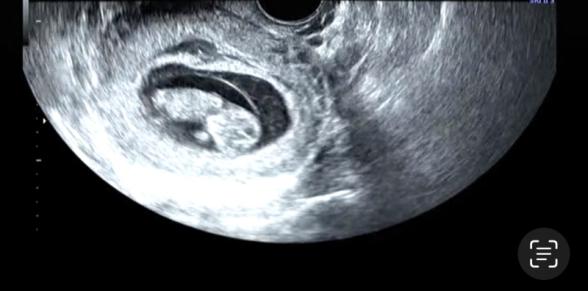

この角度この画角でしか診てもらえてないのですが、この角度でも浮腫んでたらわかるものなのでしょうか?

そうですね。お写真からですと、なかなかはっきりとしたことは明言できませんが、おそらくむくみは診ているのではないかと思いますよ。もし、おかかりつけの産院に対して思われるところがあるのでしたら、産院を変えていただくのはいいと思いますが、人気の産院などは、初期健診の際に分娩予約を取らないといっぱいになってしまったりするところもありますので、事前にお調べいただいて、お問い合わせいただいてから、転院を決められた方が安心かもしれませんね。